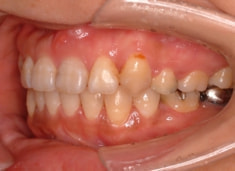

治療前

治療開始時